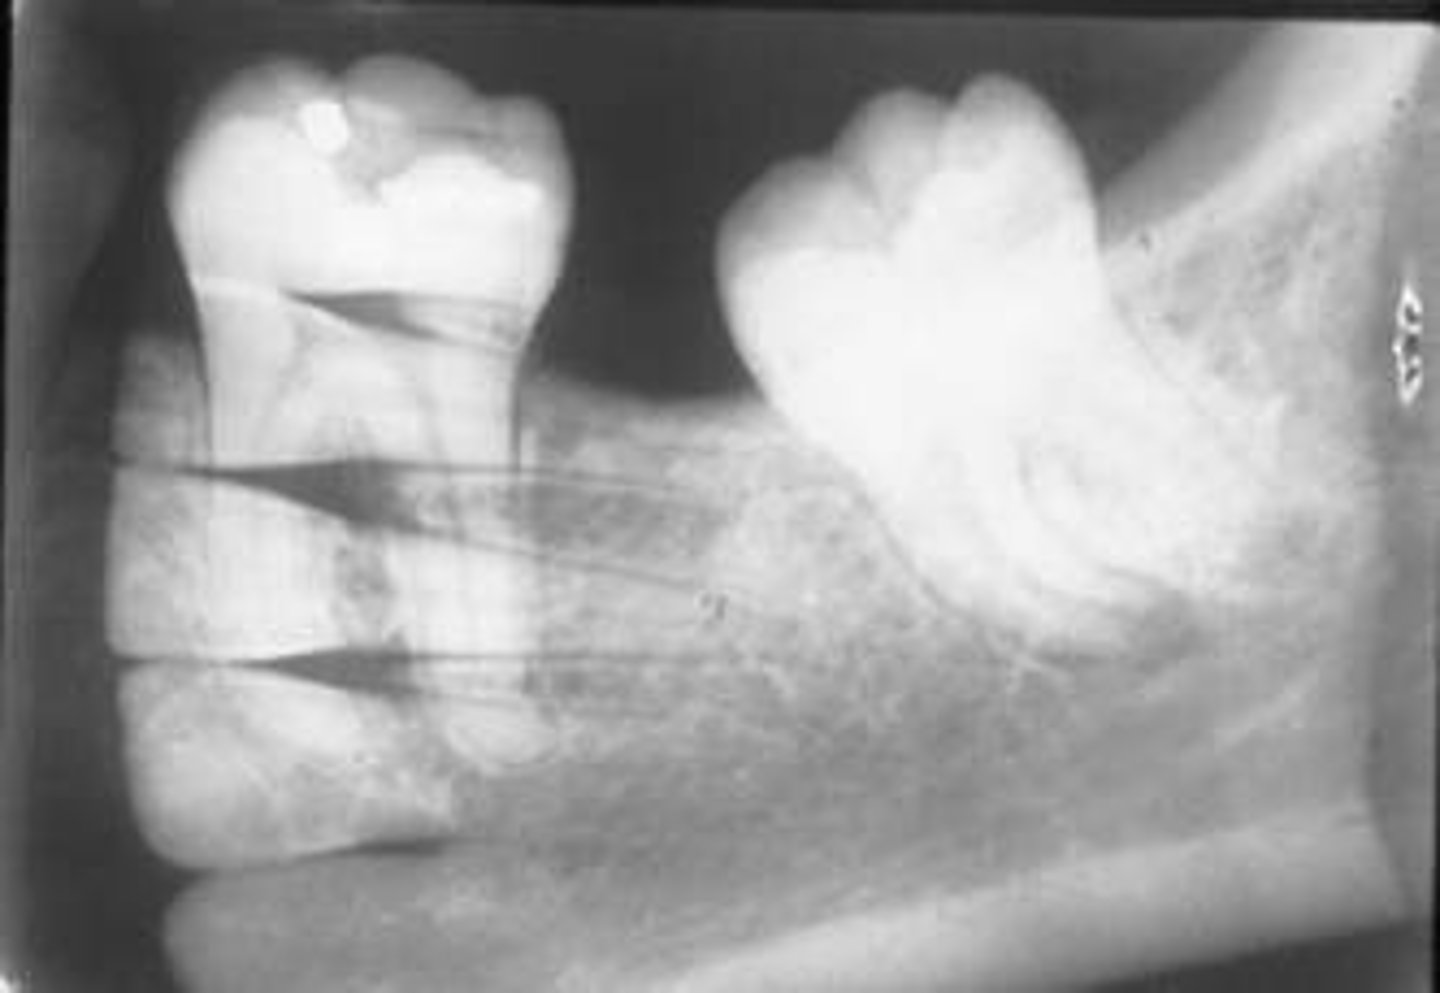

incorrect placement of molar bite wing

third molar regions not visible on the image

receptor too far forward

make sure anterior edge of the receptor is at the midline of the mandibular second premolar

center the molar bite wing over the mandibular second molar